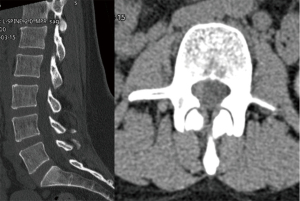

Computed tomography (CT) imaging of her spine showed an asymmetric hyperattenuating soft tissue density within the right lateral aspect of the spinal canal at the L2–3 level (Figure 1). Magnetic resonance imaging (MRI) with and without gadolinium showed a non-enhancing soft tissue signal intensity within the right lateral epidural space at L2–3 containing minimal fat signal on the pre-contrast T1-weighted images, causing mild central stenosis with mild to moderate right foraminal stenosis (Figure 2). The lack of contrast enhancement and the relatively well-defined borders made malignancy a less likely diagnosis. Epidural hematoma could not be excluded, but the heterogenous soft tissue signal in conjunction with her history of sickle cell anemia without prior trauma were less consistent. The radiographic findings were therefore suggestive of an epidural EMH lesion.